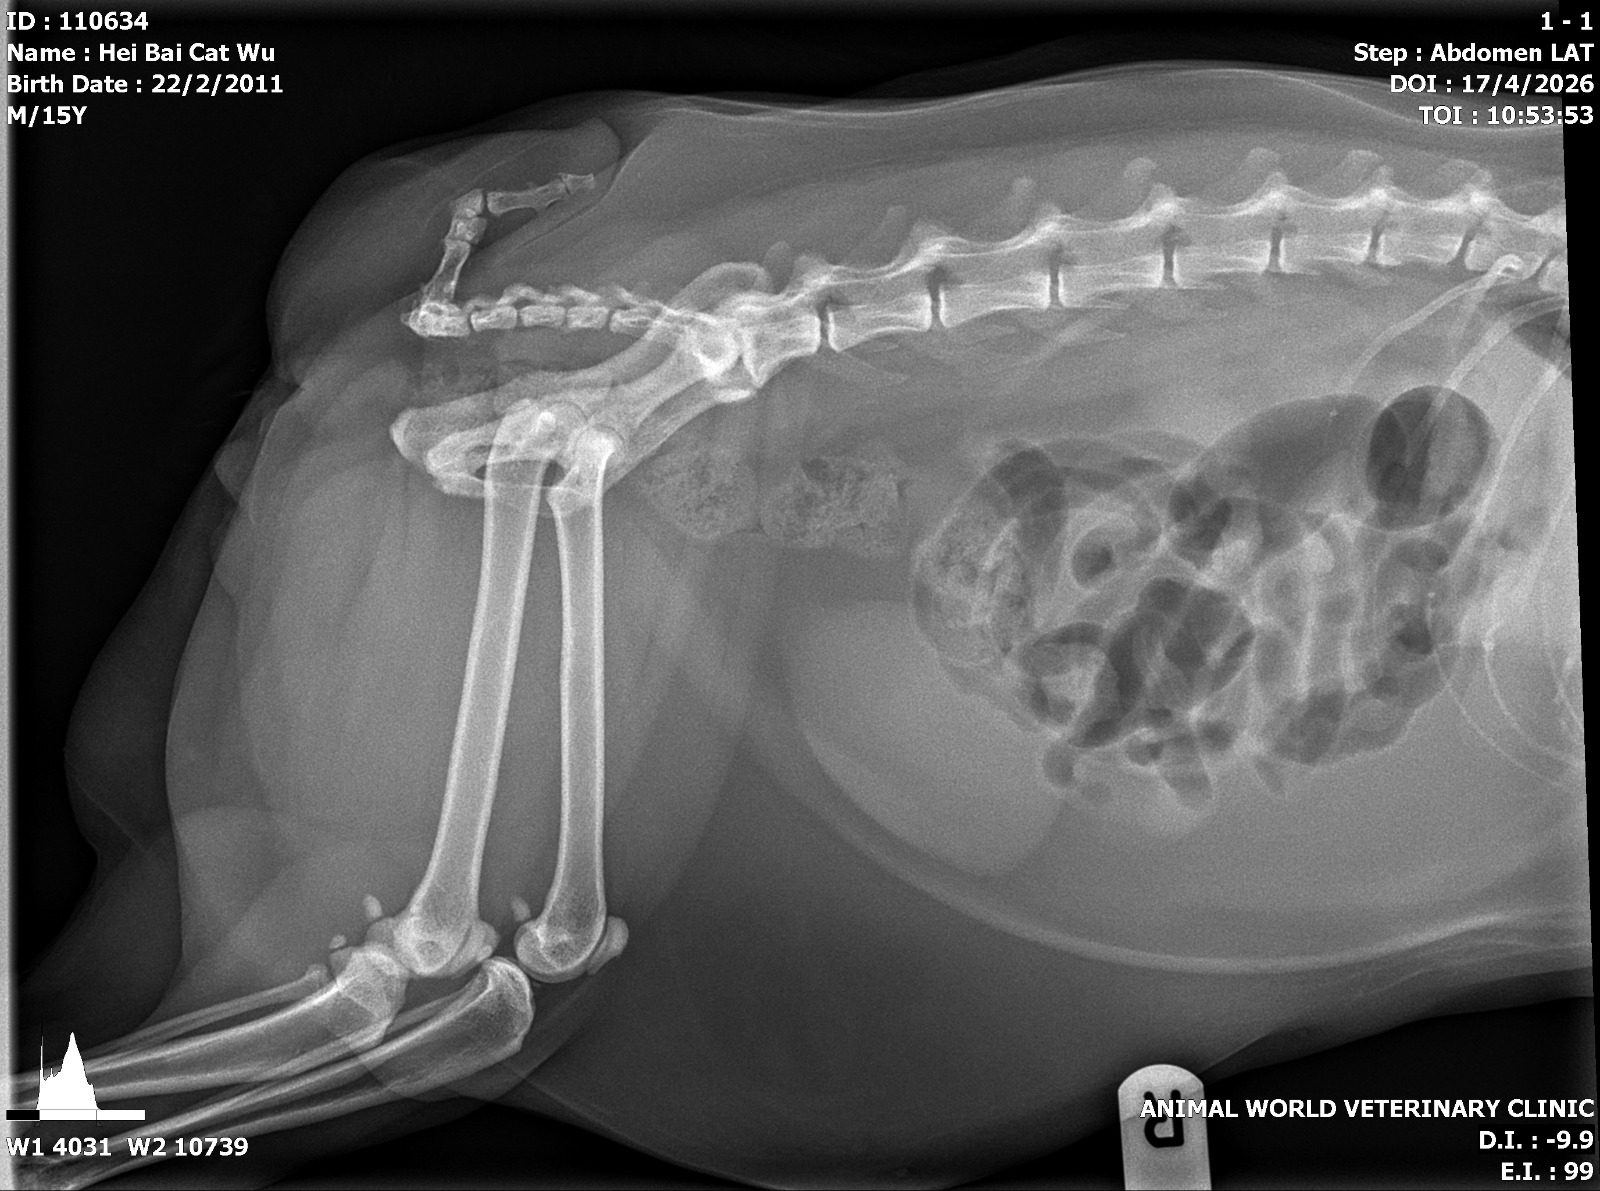

“Green arrow – dilated loop of gut, either gassy colon or SI bt need VD to confirm

Yellow arrow – area of bright white ie sclerosis could be lower back/pelvis area arthritis, monitor for any dragging of backpaws in case of nerve pinching”